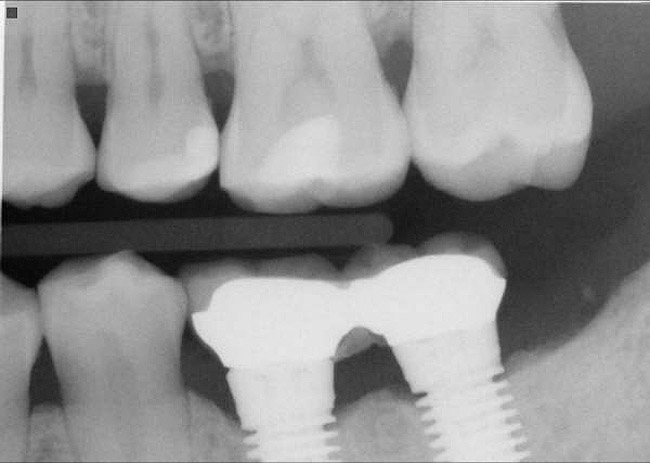

Figure 12  Horizontal spacing needed between the natural tooth and the implants and between the adjacent implants.

Figure 12

Figure 13  Radiograph depicting the necessity of horizontal placement parameters to prevent vertical defects from becoming horizontal defects.

Figure 13